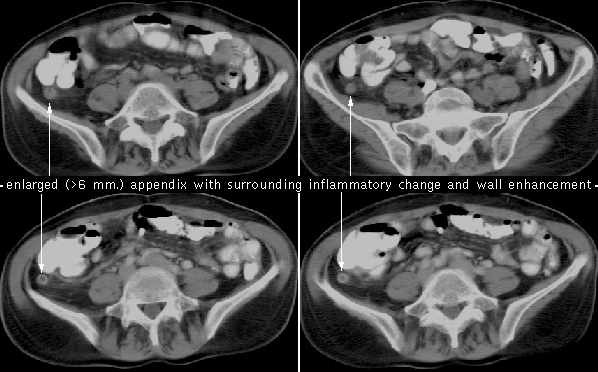

A twenty-five year-old female medical student presents to the emergency room with a complaint of "colicky" periumbilical pain which has intensified over the last 6-8 hours and now has started to migrate to the right lower quadrant. The patient reports some initial nausea, and as the pain has increased she has had increasing emesis and anorexia. Physical exam demonstrates the patient has no distension, auscultation reveals hyperactive bowel sounds, and on palpation the patient demonstrates abdominal guarding and rebound tenderness, and the muscles of the anterior wall in the right lower quadrant are rigid. In addition, the patient has a low-grade fever, and laboratory tests reveal a rising white blood cell count. The attending determines that the patient has acute appendicitis and prepares to take the student to the O.R. for an appendectomy. The surgeon asks you the following questions regarding the surgery.